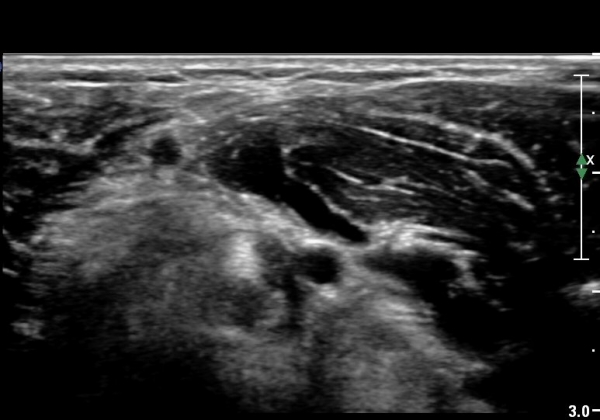

¿ìÃø ÆÈ²ÞÄ¡ ¾ÕÂÊ¿¡¼­ ÀÌµÎ¹Ú±Ù°Ç È¾´Ü¸é°Ë»ç¿¡¼­ À̵ιڱٰǿ¡ ƯÀÌ ¼Ò°ßÀ» º¸ÀÌÁö ¾Ê(±×¸² 1, 2).

ŽÃËÀÚ¸¦ Á¶±Ý ¸»´ÜÀ¸·Î À̵¿Çϰí ŽÃËÀÚ¸¦ ¸Ó¸®ÂÊÀ¸·Î ±â¿ïÀÌ´Ï À̵ιڱٰÇÀÌ ¶Ñ·ÈÇÏ°Ô °üÂûµÇ´Âµ¥ À̵ιڱٰÇÀÇ ºÎÁ¾ÀÌ °üÂûµÊ(±×¸² 3).